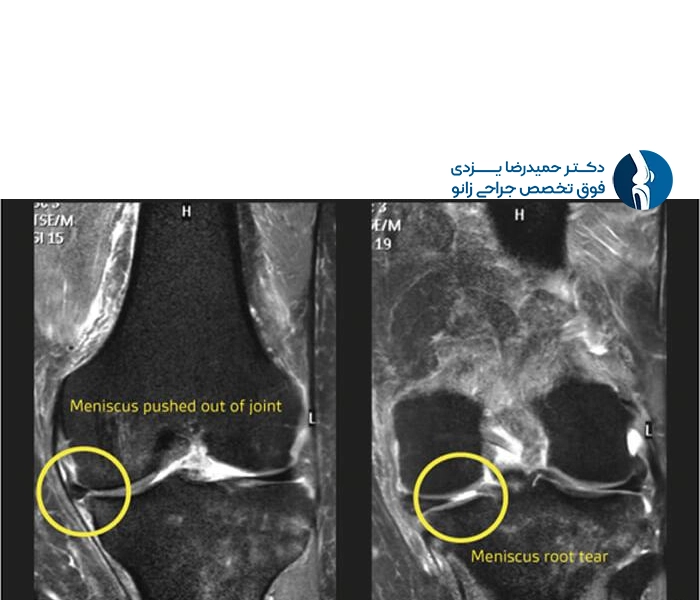

متخصص با استفاده از معاینه بالینی و ابزارهای تشخیصی دقیق مانند MRI، نوع و شدت پارگی را تعیین میکند و بر اساس آن، مناسبترین روش درمانی (مانند فیزیوتراپی، دارودرمانی، یا جراحی) را تجویز مینماید.

همچنین، توانایی تشخیص دقیق از طریق معاینات بالینی و تفسیر درست آزمایشات تصویربرداری، از معیارهای اصلی انتخاب بهترین پزشک است.